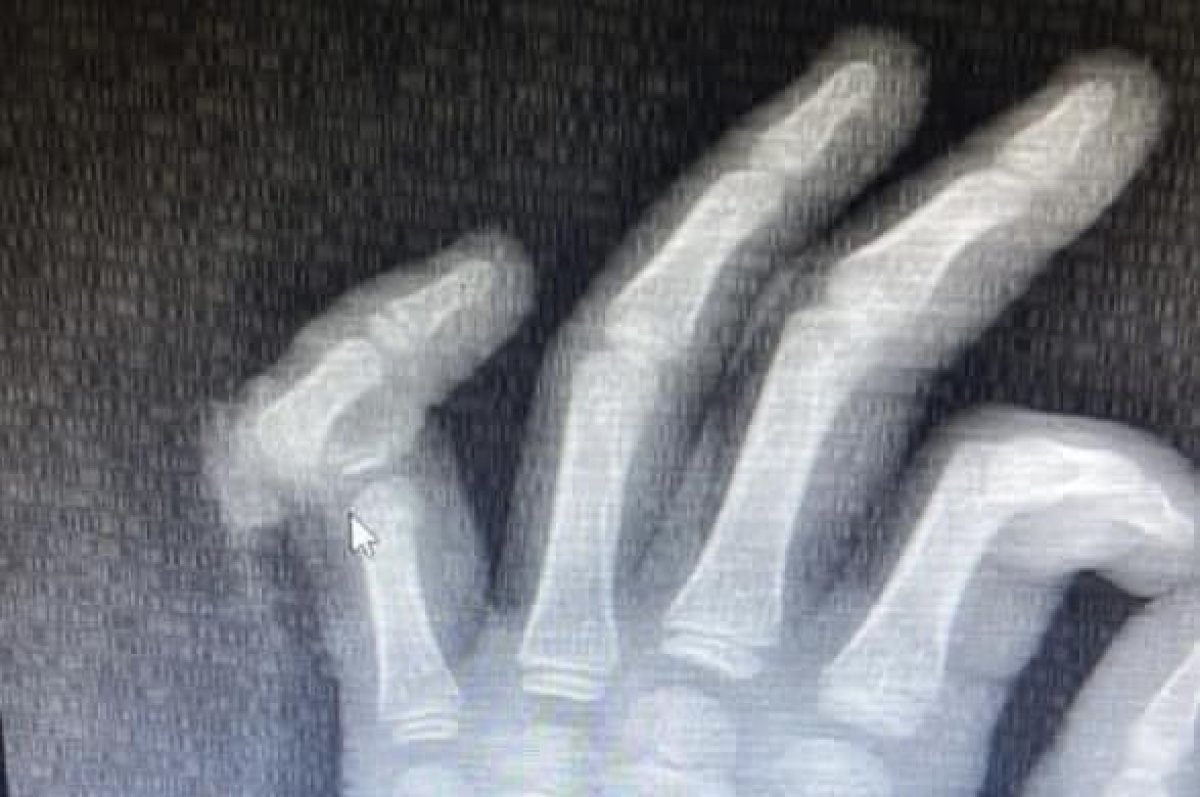

Оторванный палец пришили ребёнку в Алматы

Девятилетний мальчик остался без мизинца на руке из-за уличной травмы. Шансы спасти палец были крайне малы, к тому же врачи детской больницы № 2 Алматы впервые взялись за такой случай, передает Liter.kz.

Экстренная операция длилась пять часов, одновременно работали специалисты двух профилей – травматолог и два микрохирурга.

Для проведения такой операции необходима современная микрохирургическая техника: требуется микроскоп, микрохирургический инструментарий и очень тонкий шовный материал, который сложно увидеть невооруженным глазом, все это имеется у нас во второй детской больнице. Нам пришлось шить сосуды диаметром 1.2 мм. Без должной подготовки, оборудования, инструментов и расходных материалов проведение таких операций невозможно, – рассказал заведующий отделением травматологии Ерлан Садырбалин.

Но все прошло благополучно. Еще восемь дней пациента наблюдали в стационаре. Палец полностью прижился. Родители ребенка называют работу врачей чудом.